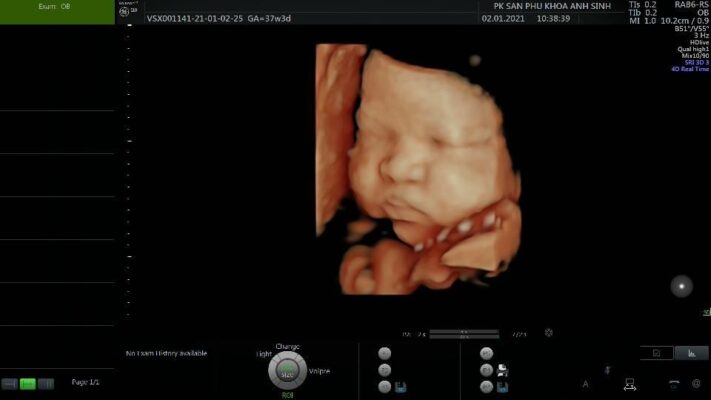

Nơi hạnh phúc vuông tròn – Sản phụ khoa Anh Sinh | Uy tín – Chuyên nghiệp – Thân thiện

Nếu đang tìm kiếm một địa chỉ uy tín để khám sản phụ khoa tại...